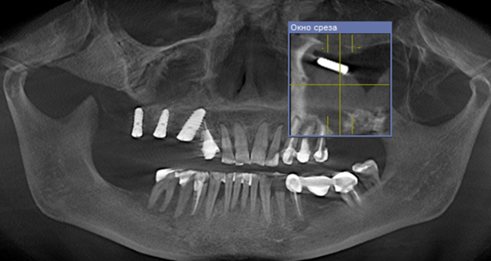

Одним из часто встречающихся осложнений операции имплантации и удаления зубов на верхней челюсти является перфорация дна верхнечелюстного синуса (рис. 1, 2, 3). Точное знание анатомического строения пазухи позволяет избежать подобных осложнений [Romandini et al., 2021; Putra et al., 2022]. Кроме того, с возрастом происходит изменение соотношения объема губчатого и компактного костного вещества в области премоляров и моляров верхней челюсти, что является предрасполагающим фактором перфорации дна синуса [Papadakis et al., 2021; Wei et al., 2021].

Рис. 1. Перфорация дна верхнечелюстной пазухи справа и проталкивание имплантата

в полость синуса

Fig. 1. Perforation of the bottom of the maxillary sinus on the right and pushing the implant

into the sinus cavity